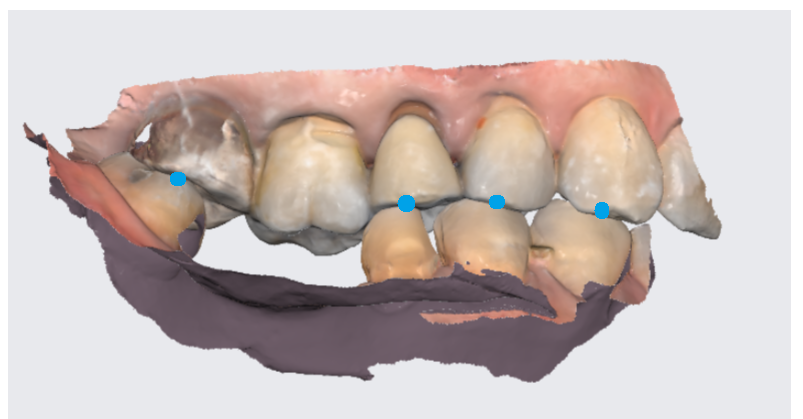

파란색 점이 환자분이 물리는

교합을 나타내는데요.

3d로 스캔해두기에

상,하,좌,우

아래에서 본 모습

위에서 본 모습

360도 확인이 가능합니다!!!

때문에 보철을 어떻게 만들지

제가 디자인 하고

찾아볼 수 있는것이 장점입니다!